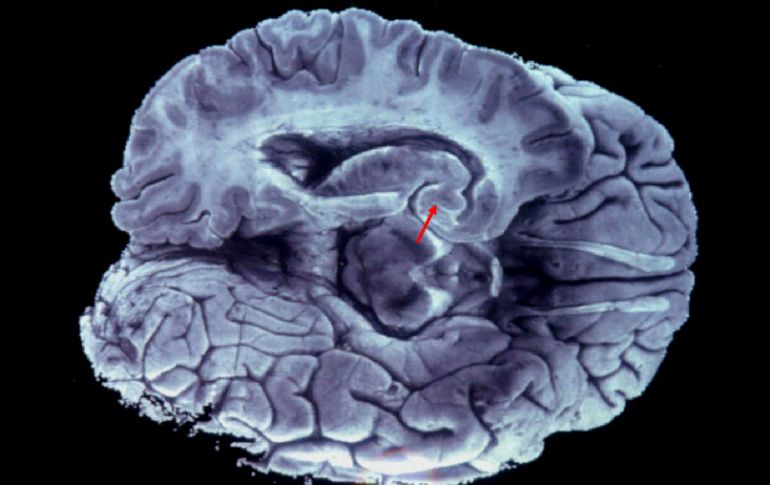

Internacional | Personas y estudiantes podrían habérselos estado llevando durante años Se pierden 100 cerebros de Universidad de Texas El cocurador de la colección sugiere que personas se podrían habérselos llevado durante años Por: AP 2 de diciembre de 2014 - 21:02 hs Uno de los órganos presumiblemente pertenece al asesino múltiple Charles Whitman. EFE / ARCHIVO AUSTIN, ESTADOS UNIDOS (02/DIC/2014).- La Universidad de Texas campus Austin ha perdido alrededor de un centenar de cerebros. Esa cifra representa la mitad de los especímenes que la universidad tenía en una colección de cerebros preservados en frascos con formaldehído. Uno de los cerebros extraviados presumiblemente perteneció al asesino múltiple Charles Whitman. El cocurador de la colección, el profesor de psicología Lawrence Cormack, dijo al diario Austin American-Statesman que es probable que los estudiantes y otras personas se hayan estado llevando los cerebros durante años "para sus salas de estar o para bromas del Día de Brujas". El Hospital Estatal de Austin transfirió los frascos con cerebros a la universidad hace 28 años. Aunque se eliminó la información de identificación a las muestras para proteger la confidencialidad, el cocurador Tim Schallert dijo que el cerebro de Whitman, quien mató a más de una docena de personas en la misma universidad, era parte de la colección. Temas Norte América Estados Unidos Curiosidades y absurdos Cerebro Lee También La paz siempre es una buena noticia Revelan llamada al 911 con que se reportó la muerte de Diane Keaton SMN advierte lluvias y bajas temperaturas en México esta semana ¿Cuáles son los beneficios de tomar jugo de betabel y cómo se prepara? Recibe las últimas noticias en tu e-mail Todo lo que necesitas saber para comenzar tu día Registrarse implica aceptar los Términos y Condiciones